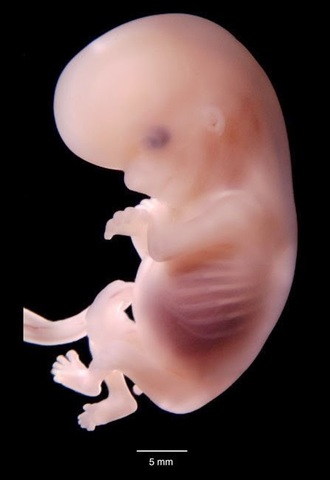

Semana Ocho

Ya tiene párpados,labio superior, nariz y orejas se están empezando a formar. El cuerpo se está alargando, pueden reconocerse lo que serán brazos y piernas, y es posible ver el esqueleto a través de su piel, que es translúcida.El esqueleto está formado por un cartílago suave todavía, no son huesos.

Hasta ahora, el embrión dependía del saco vitelino que, según se cree, le proporciona nutrientes.Entonces cuando la placenta asume la función de alimentarlo a través del cordón umbilical